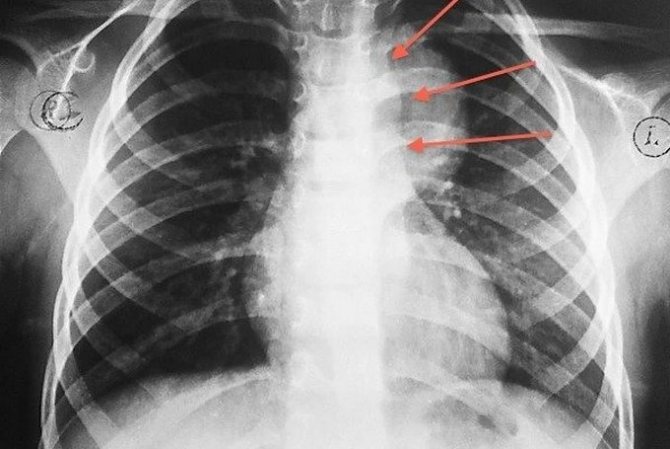

Рентгеновские снимки тератомы средостения: Диагностика и лечение

Раздел: Фотоэссе